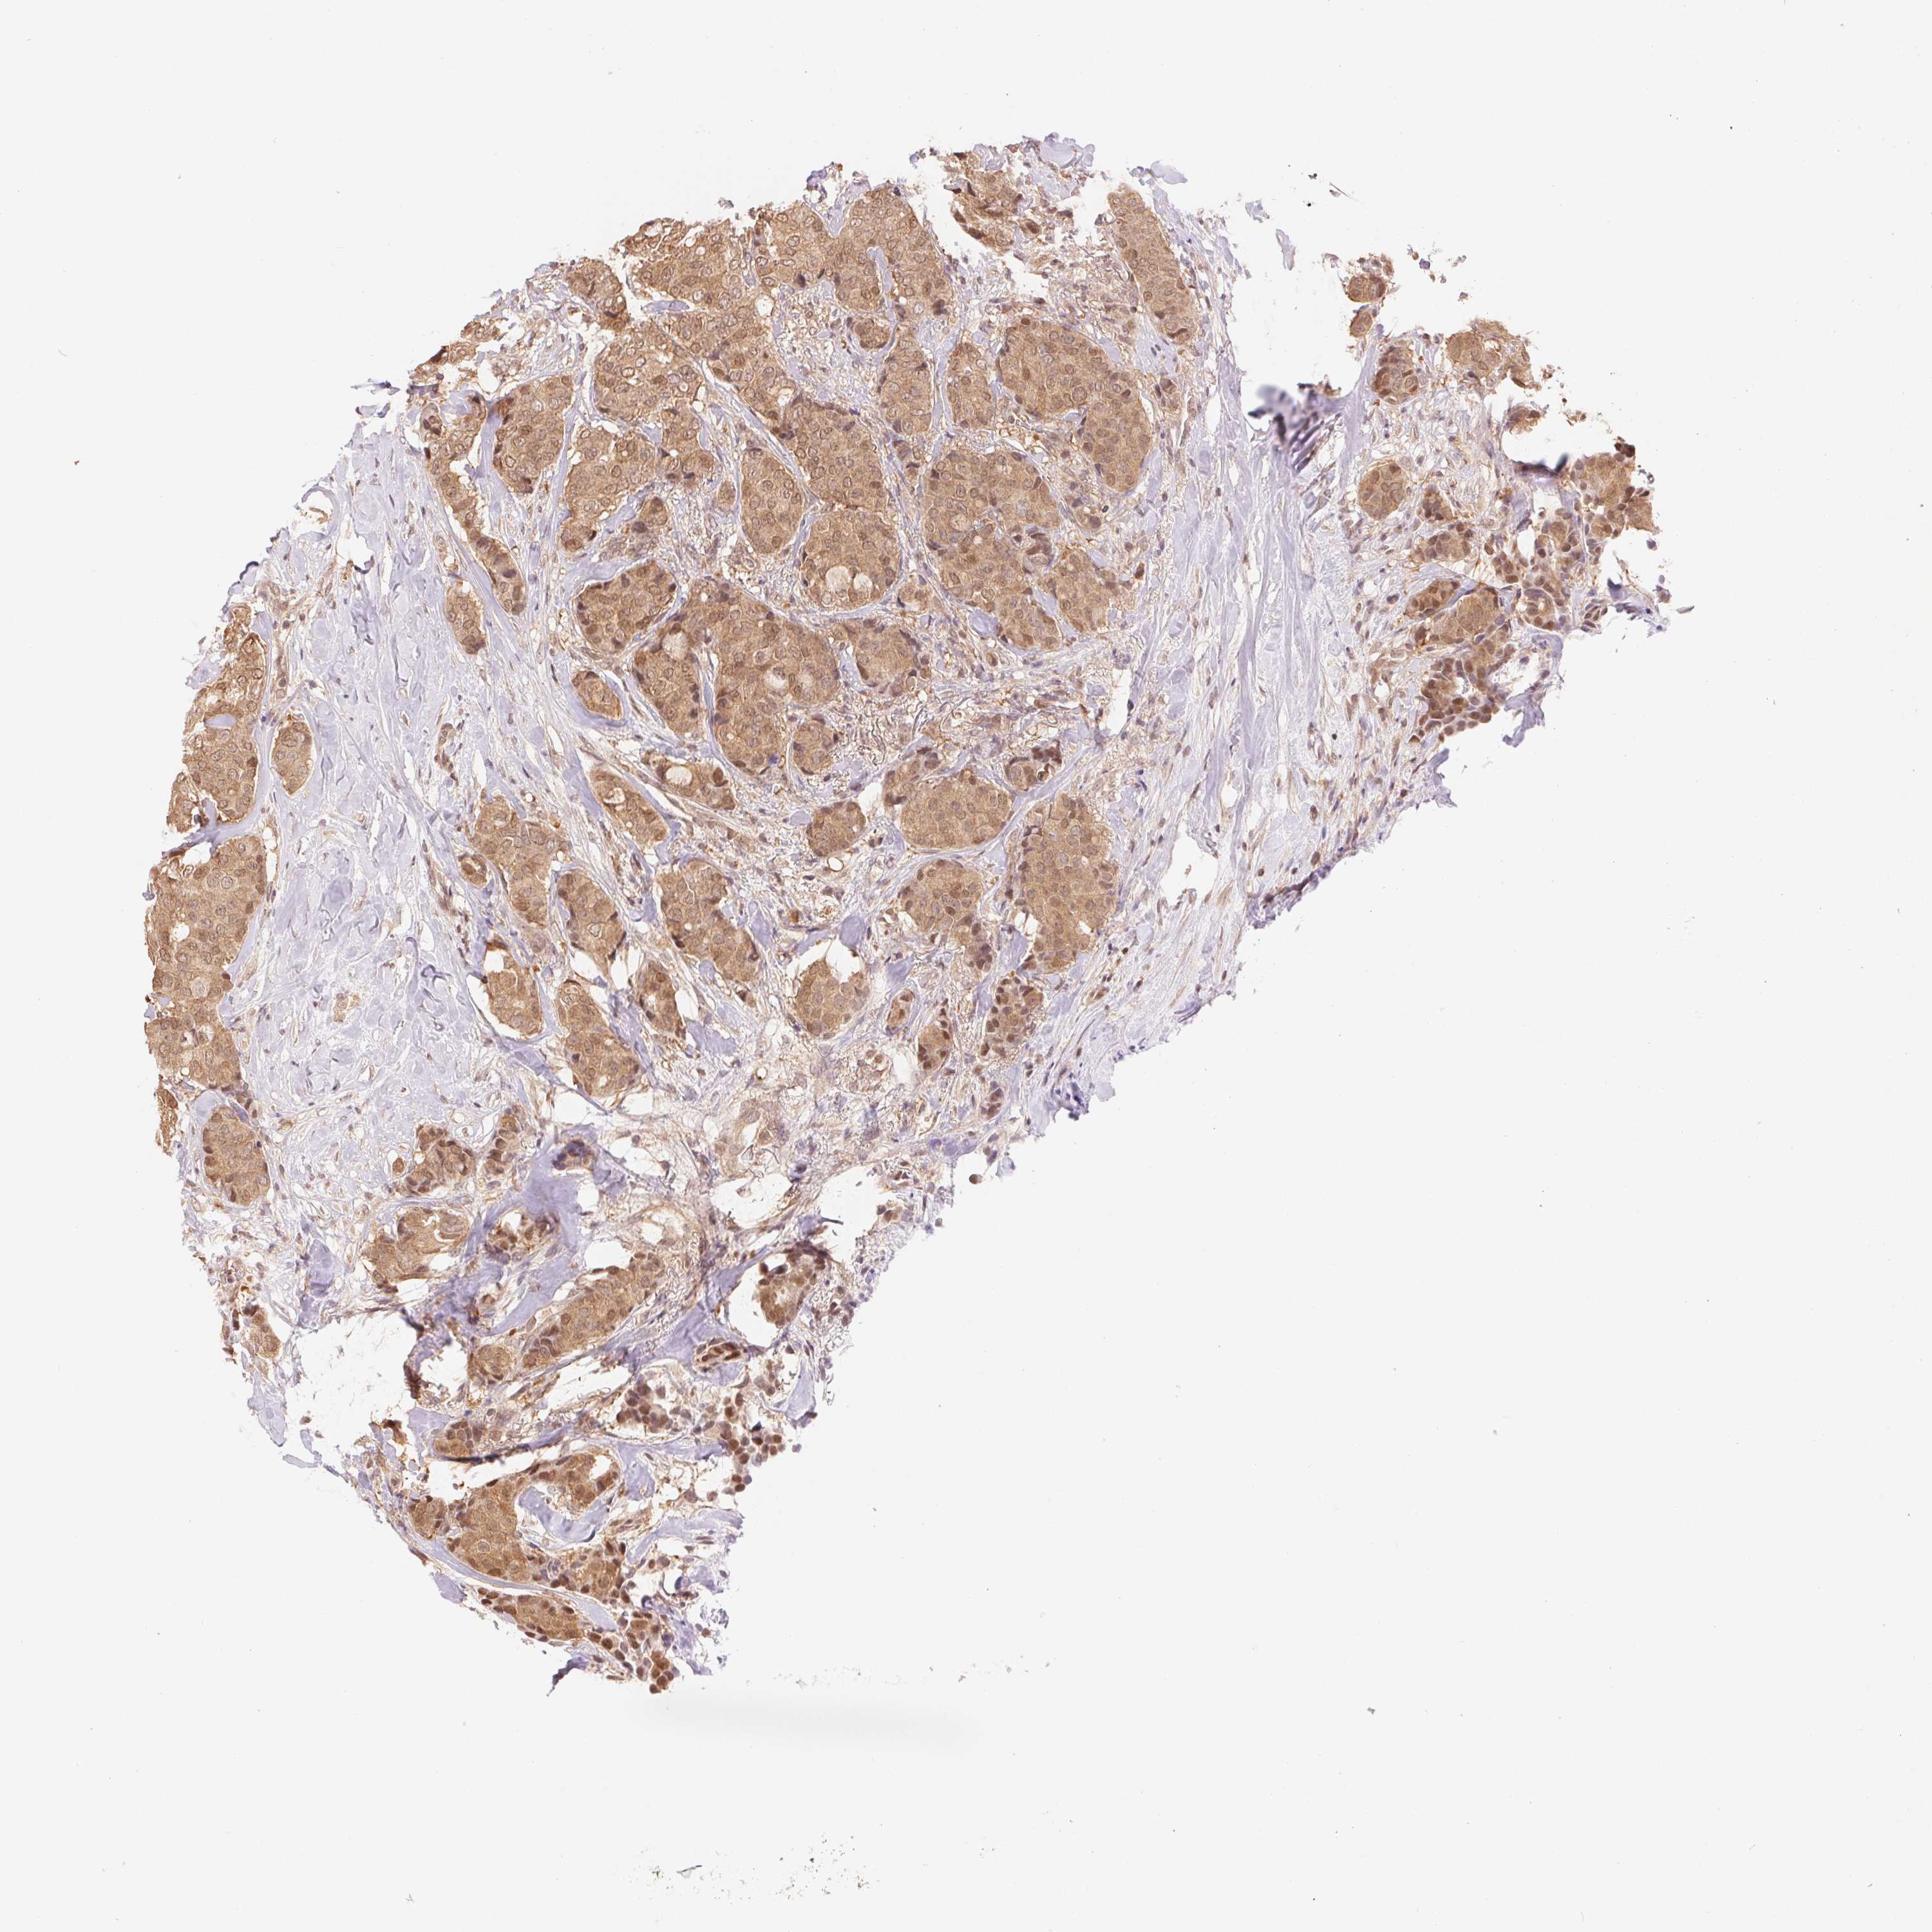

BRCA TCGA BRCA VALIDATION PROTEIN EXPRESSION

ANTIBODIES

AND

VALIDATION